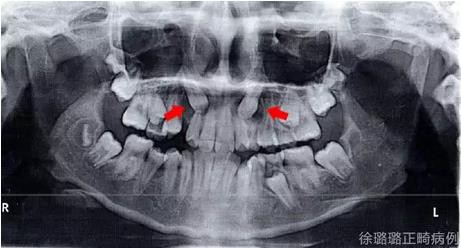

影像學(xué)檢查

X 線檢查:替牙列,上頜雙側(cè)尖牙埋伏阻生(含牙囊腫),四顆第三恒磨牙牙胚存在。

前牙 CT 檢查:上頜雙側(cè)尖牙埋伏阻生——雙側(cè)尖牙的牙冠均在側(cè)切牙根方的唇向位。

CT 片結(jié)果顯示,上頜雙側(cè)側(cè)切牙與尖牙位置較近,因此早期沒有粘結(jié)雙側(cè)側(cè)切牙托槽,以防止正畸加力對牙齒造成根尖吸收。